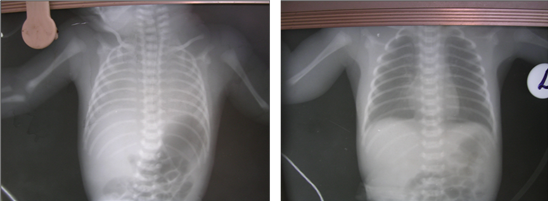

- 11. Humidification...

12. Radiologic monitoring